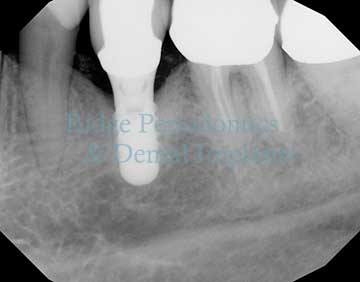

Laser Periodontal Regeneration

Advanced laser therapy for treating peri-implant disease and maintaining the health of dental implants.